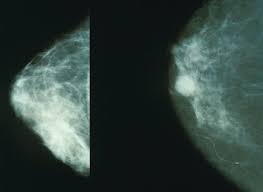

مراحل تطور سرطان الثدي بالصور ويب طب

اعراض سرطان الثدي اسبابه وتشخيصه وعلاجه الطبي